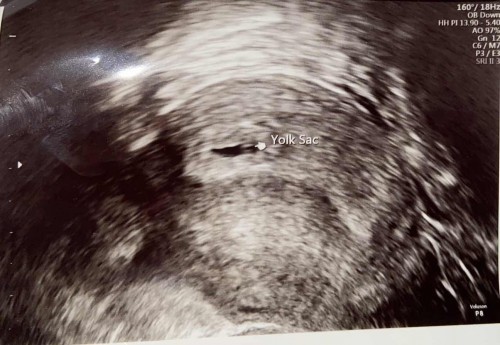

วันนี้ไปอัลตราซาวมา ฝากครรภ์ครั้งแรกค่ะ หมอบอกอายุครรภ์น่าจะเดือบๆ 5 สัปดาห์ ภาพอัลตราซาวด์แบบนี้ ถุงตั้งครรภ์ปกติไหมคะ

มึแม่ๆท่านไหนถุงตั้งครรภ์คล้ายๆแบบนี้บ้างคะ เราแอบกังวลค่ะ

อายุครรภ์น้อยต้องอัลตร้าซาวด์ทางช่องคลอดถึงจะเห็นชัดเจนนะคะแม่